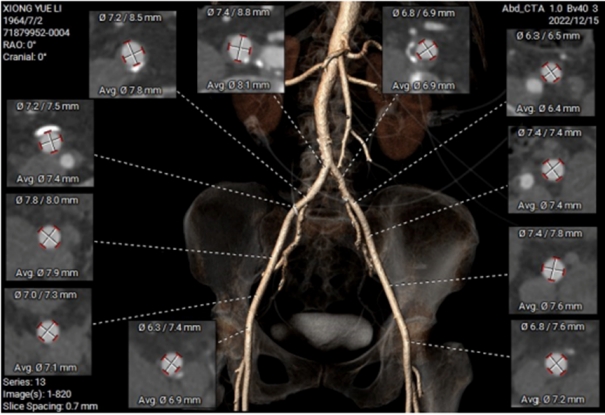

经过手术团队反复评估和研讨后,最终考虑选用右股动脉为主入路,导丝过瓣后,植入VitaFlow Liberty TAV30瓣膜,用DSR30电动可回收输送系统确保瓣膜的精准定位和释放,术后结合造影和超声,再评估是否需要瓣中瓣做为预案。